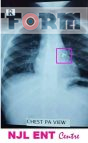

চিকিৎসকের পরামর্শ মোতাবেক শিশুর বুকের এক্সরে করিয়ে রিপোর্টে তার শ্বাসনালীতে একটি বোতামের অস্তিত্ব ধরা পড়ে।

পরবর্তীতে বিস্তারিত জিজ্ঞাসায় জানা যায়, উক্ত শিশু দেড় মাস আগে কৌতুহল বশত জিন্সের প্যান্টের একটি বোতাম গলাধঃকরণ করেছিল।

এমতাবস্থায় সময়োপযোগী চিকিৎসার জন্য উক্ত শিশু বিশেষজ্ঞ চিকিৎসক রিয়াদকে রেফার করেন সিলেটের NJL ENT Centre -এ। অতঃপর সেখানে কর্মরত ” নাক কান গলা ও হেড নেক সার্জারি” বিভাগের সহকারী অধ্যাপক ডা. নূরুল হুদা নাইম ব্রঙ্কোস্কোপির মাধ্যমে বোতামটি বের করে আনতে সক্ষম হন।